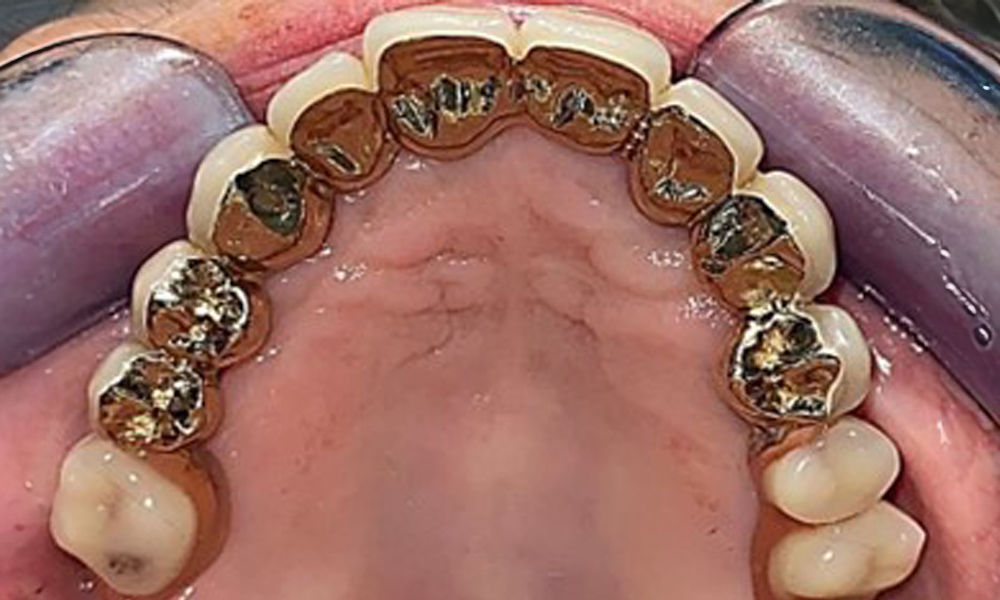

Occlusal view: Maxilla with tooth and implant-supported telescopic prostheses.

Fig. 2: Occlusal view: Maxilla with tooth and implant-supported telescopic prostheses

The patient was fitted with a combined removable maxillary telescopic prosthesis more than 25 years ago (Fig. 1, Fig. 2, Fig. 3) and is very happy with her dentures. The patient has an adequate fixed denture for the mandible (Fig. 4).

The dental findings are as follows: Combined removable implant and tooth-supported telescopic prostheses on implants 15, 13, 21, 23, 24, 25 and tooth 11 (Fig. 1, Fig. 2, Fig. 3). The patient was fitted with a fixed mandibular denture. Adequate bridges were present over 37 to 34 and 45 to 47 (Fig. 4), the crown margins were intact and there were no active caries. A composite filling with a marginal gap was present on tooth 43. There was mandibular gingival recession, exposing 1 to 3 mm of root surface. This also applies to 11.